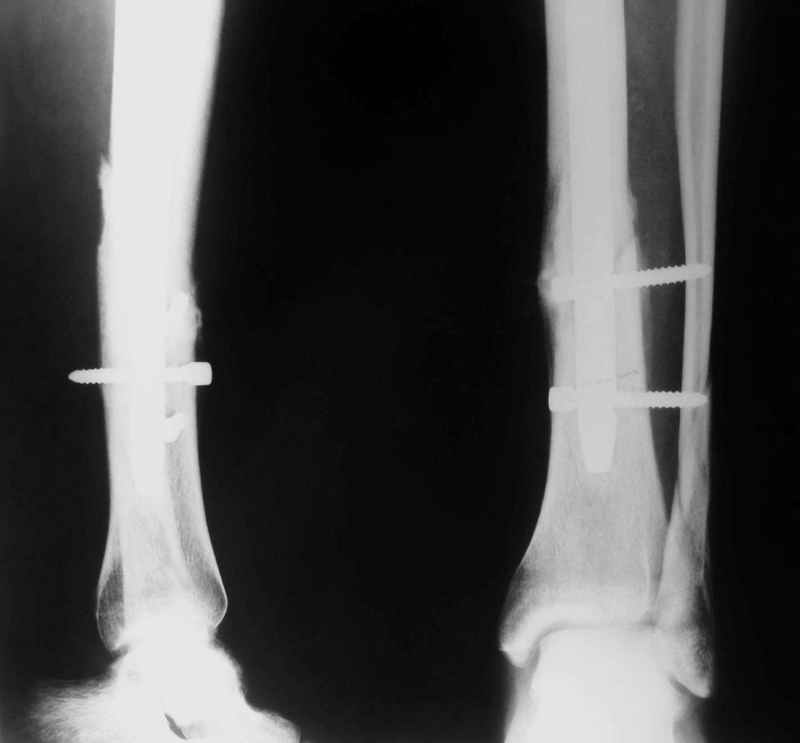

В дистальном отломке три винта( два медио-латеральных и один вентро-дорзальный).

Медио-латеральные вынты - мимо блокирующих отверстий фиксатора, вентро -

дорзальный винт - в отверстии.

Проблемы с верхним дистальным медио - латеральным винтом - он в линии перелома (

перелом косой).

То есть в дистальном отломке всего один запирающий винт. Маловато.

Если в проксимальный отломок стержень сел туго, это не мешает дистальному (широкому и короткому, раз дистальное отверстие уже на уровне перелома) быть нестабильным, особенно если он фиксирован лишь одним винтом.

Выполненный остосинтез нестабилен. Штифт надо заменить по "размеру" на солидный, дистльно три запирающих винта. Успехов!

Перелом спиральный, то есть низкоэнергетический, так что со сращением дело обстоит уже неплохо, лишь бы "костоеда" не развилась. Отломки выглядят уже стабилизированными костной мозолью, так что довводить винты, наверно, уже незачем. Разве что при клинической оценке подвижность еще есть - тогда можно для стабилизации наложить простейший аппарат, не опасаясь контакта его элементов с гвоздем, поскольку места в дистальном метафизе оставлено более чем достаточно.